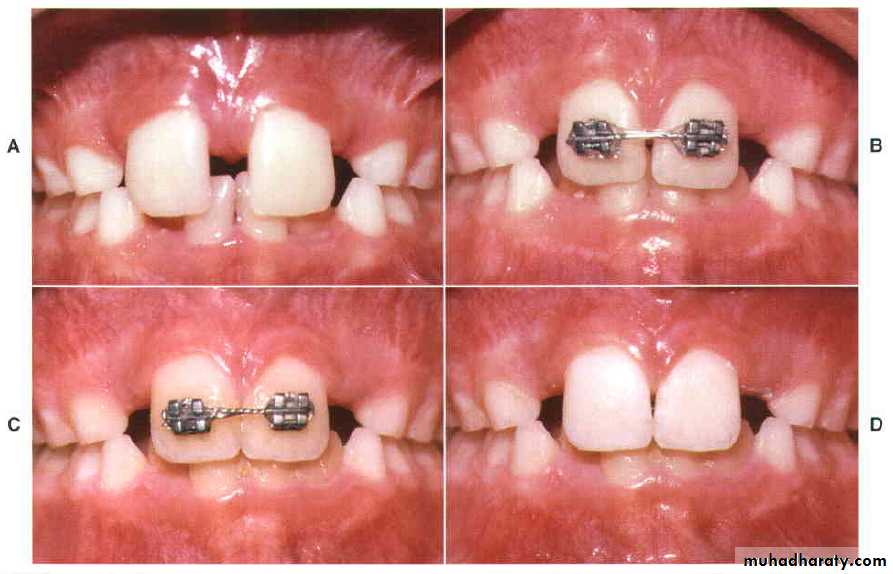

69

Closure of a diastema with a fixed appliance, immediately after space closure, the teeth are retained, preferably with, (D) a fixed lingual retainer at least until the permanent canines erupt.